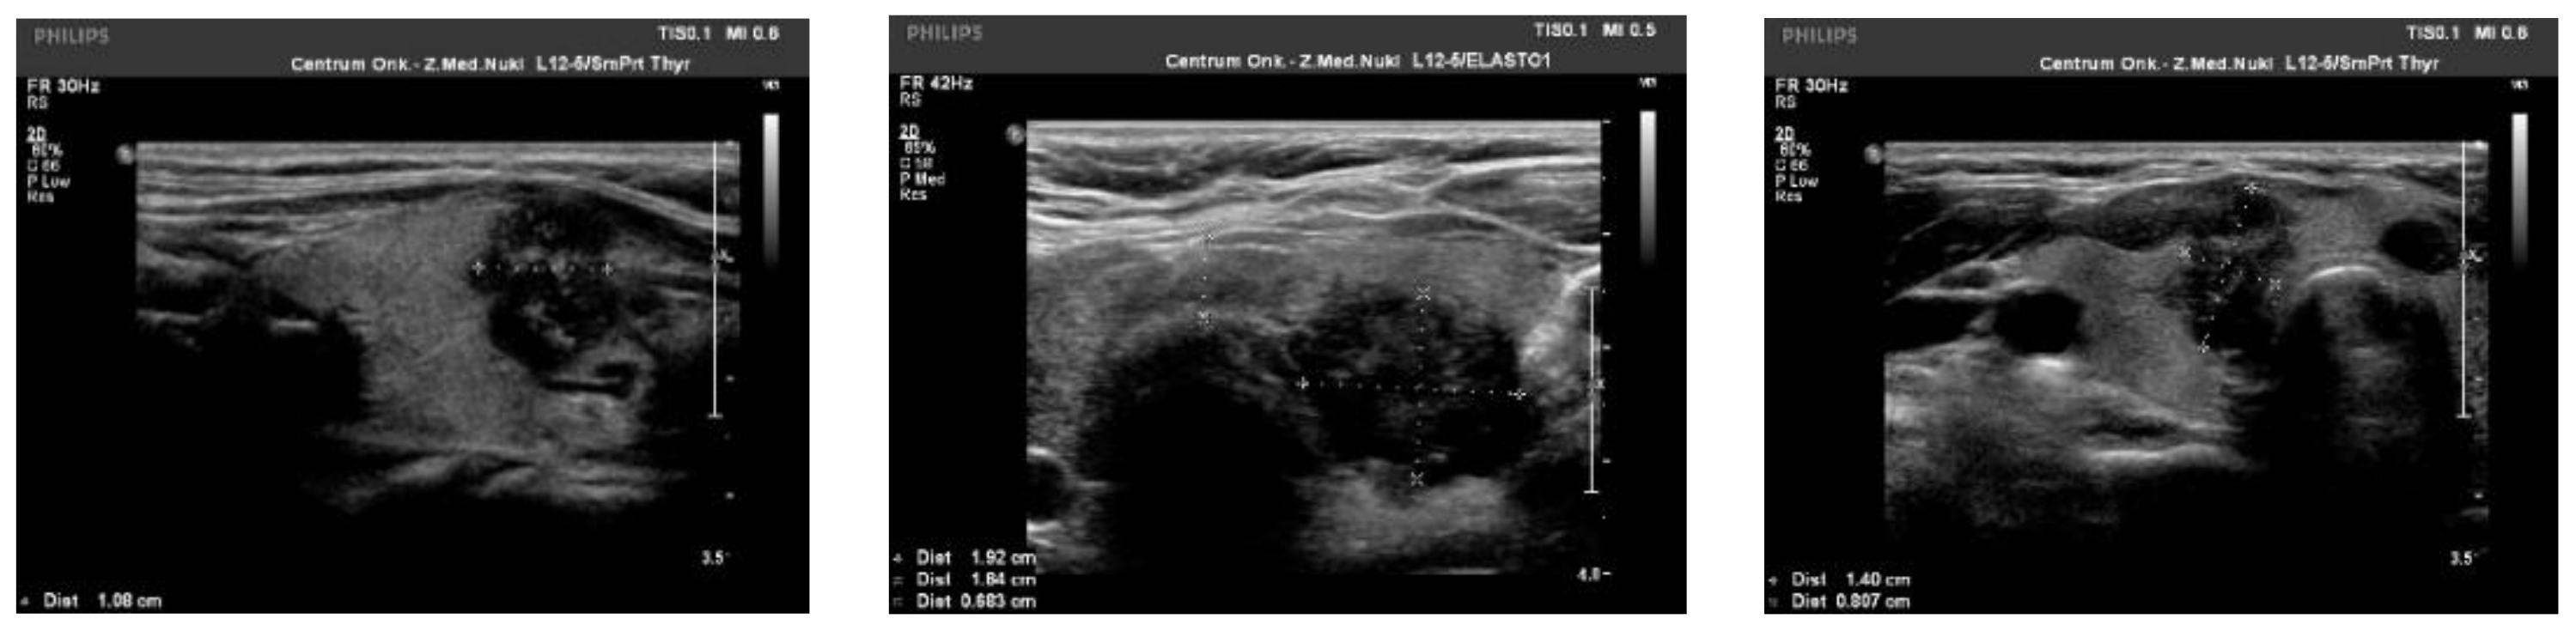

We observed the strongest correlation between hypoechogenicity (p-value < 0.05) and BRAF V600E positivity, although four more malignancy-associated features (taller-than-wide shape, blurred margins, microcalcifications, and absence of “halo”) were also more frequent in the BRAF V600E (+) group. PTC risk increased with a higher EU-TIRADS score (p-value = 0.04). US images of BRAF V600E (+) and BRAF V600E (−) PTCs are presented in Figure 2 and Figure 3, respectively.

Figure 2.

US image of BRAF V600E positive PTCs: solid structure (2 points), deeply hypoechogenic, (3 points), taller-than-wide orientation (3 points), blurred margins (2 points), microcalcifications (3 points)—13 points = TIRADS 5.